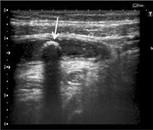

Imágenes: La tomografía contrastada es el estudio de mayor precisión diagnóstica; sin embargo, en las mujeres jóvenes se prefiere la ecografía como estudio inicial (ESSALUD 2010, 2014), ante la probabilidad de una gestación en curso. Hallazgos: diámetro apendicular > 6 mm, pared ≥ 2mm. La presencia de coprolito o líquido libre en cavidad peritoneal refuerza el diagnóstico. La tomografía contrastada también es el estudio de elección ante la sospecha de masa apendicular.

El estudio de imágenes de elección es la ecografía. Entre sus hallazgos, se observa:

Pared vesicular mayor o igual a 4 mm

Longitud o ancho de la vesícula mayor o igual a 10 cm x 6 cm, respectivamente Signo de la doble pared

En ciertos casos, puede realizarse colescintigrafía, con alta precisión.